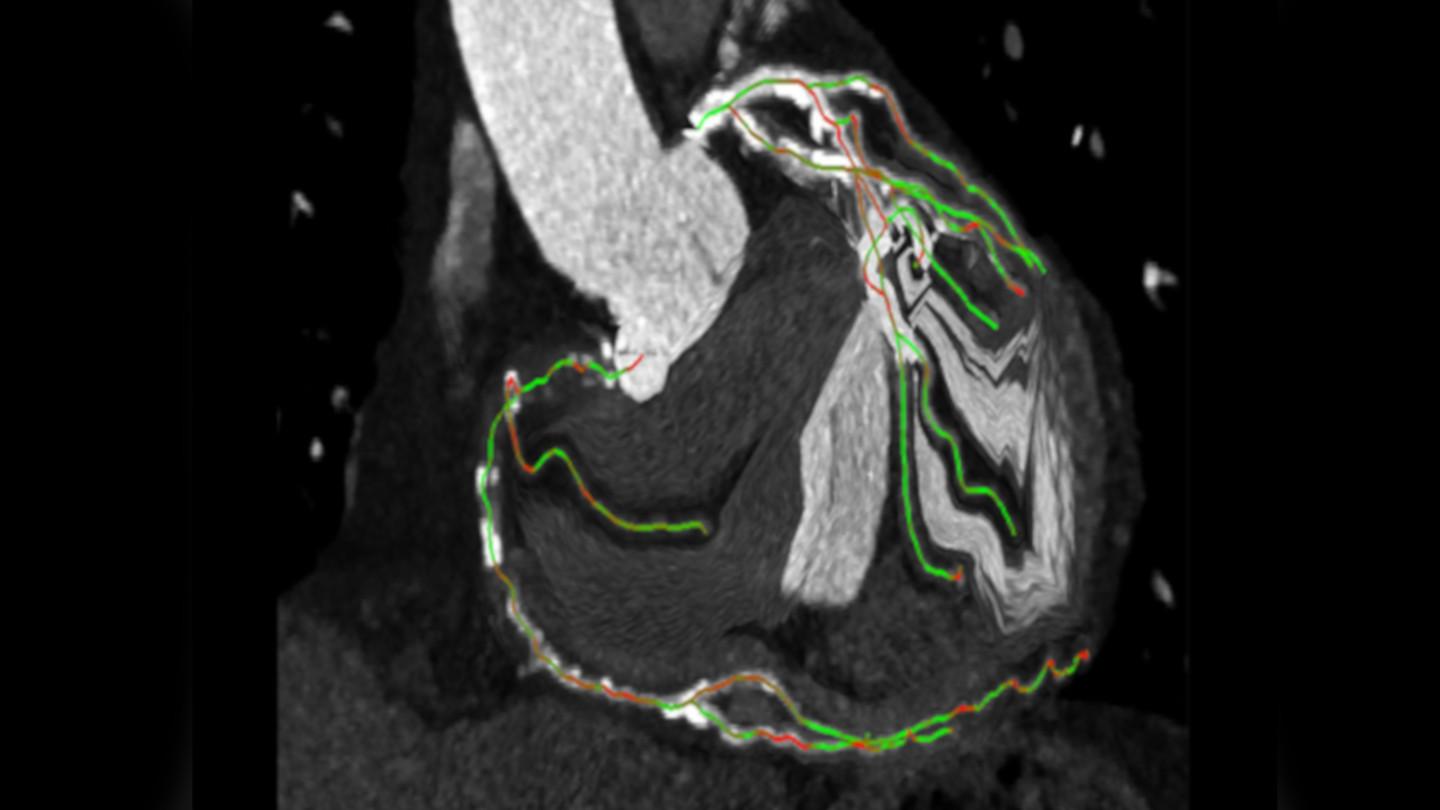

syngo CTO Guidance for automated segmentation of the coronaries

syngo CTO Guidance

Preprocedural planning using CT data

Courtesy of LMU Klinikum Munich, Germany

Expand your procedure mix by treating more CTO patients using syngo CTO Guidance for

• automated segmentation of the coronaries, centerline extraction, and color coding of the centerlines to indicate foreshortening;

• preprocedural planning of optimal angulations;

• shorter wiring times2

• reduced fluoroscopy duration2